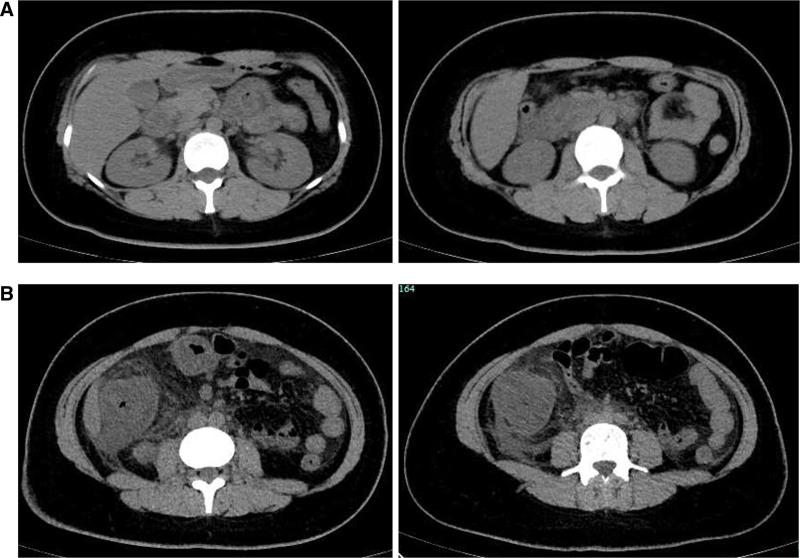

We herein report a case of a 29-year-old woman who presented with abdominal pain, nausea, and vomiting, with no history of adverse reactions to any allergens. Laboratory test results revealed a normal count of peripheral blood eosinophils. Ultrasound and computed tomography revealed thickened intestinal walls and ascites in both the abdominal cavity and the pelvic cavity. Multiple endoscopic biopsies targeting several swelling segments of the intestinal wall revealed no increase in the number of eosinophils.

Symptoms improved rapidly, and the thickened intestinal walls returned to a typical level.

我们在此报告一例29岁女性患者,她出现腹痛、恶心和呕吐症状,既往无任何过敏原不良反应史。实验室检查结果显示外周血嗜酸性粒细胞计数正常。超声和计算机断层扫描显示肠壁增厚,腹腔和盆腔均有腹水。针对肠壁多个肿胀节段进行的多次内镜活检显示嗜酸性粒细胞数量未增加。

症状迅速改善,增厚的肠壁恢复到正常水平。